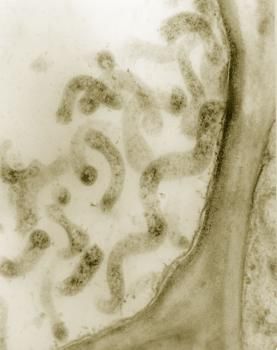

支原体是一类没有细胞壁、高度多形性、能通过滤菌器、可用人工培养基培养增殖的最小原核细胞型微生物,大小为0.1~0.3微米。它是目前发现的最小的一种细菌。由于能形成丝状与分枝形状,故称为支原体(见下图)。支原体广泛存在于人和动物体内,能够从人体分离出的支原体共有 16 种,其中7 种对人体有致病性,如导致肺部感染的肺炎支原体。